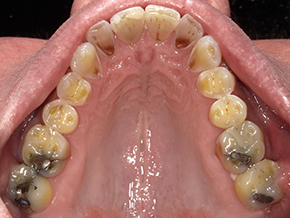

This patient is very happy with his great SureSmile® results, and we are just as happy!